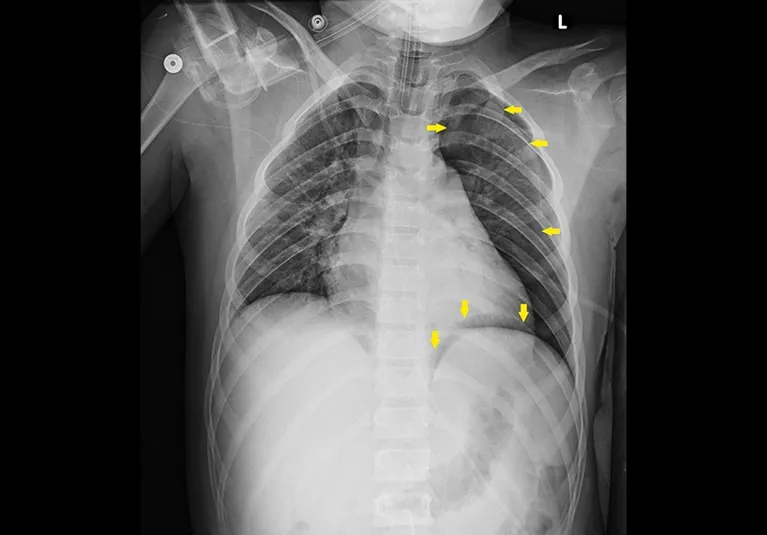

Pleural & Lung Hits - Air, Blood, Bruises

- Hemothorax (HTX): Blood in pleural space.

- CXR: Meniscus sign, opacification.

- Pulmonary Contusion: Lung "bruise".

- CXR: Patchy, non-segmental opacities (within 6 hrs, resolves 3-10 days).

Wall & Diaphragm Wrecks - Skeletal & Barrier Breaches

Rib Fractures: Most common chest skeletal injury.

Diaphragmatic Rupture:

- CXR signs: Elevated hemidiaphragm, intrathoracic bowel gas/NG tube, "collar sign".